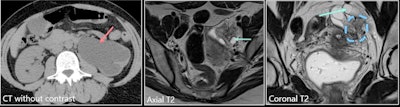

A 42-year-old woman presented with acute left lumbar region pain. She had no history of endometriosis. Left image: CT without contrast shows left hydronephrosis. Middle image: Axial T2 shows dilated left ureter. Right image: Coronal T2 shows retractile, stellar periureteral mass responsible for kidney obstruction. There was no hemorrhagic signal. The suggestion was deep infiltrative endometriosis. A nephrectomy was performed because of the complete loss of left kidney function, and it confirmed the diagnosis of left ovarian and parametrial endometriosis, with a normal ureter.Involvement of the different ureteral layers is very difficult to determine on imaging. Also, endometriosis symptoms may be secondary to upper urinary tract involvement (flank pain, obstruction), and always check for ureteral and or renal dilation (risk of renal failure if untreated)